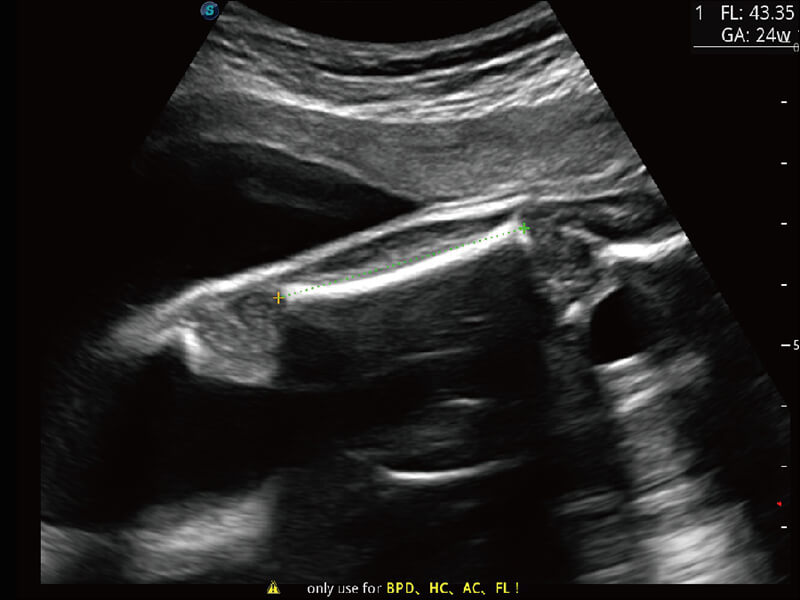

S60探头工艺,从前端信号处理每一个环节采集无损声学数据,真实还原组织原貌,再现解剖细节。

超宽频带技术,为容积成像带来优质的二维图像基础,为您呈现丰富的结构细节,栩栩如生地展示宝宝的宫内形态以及各种组织的立体结构。